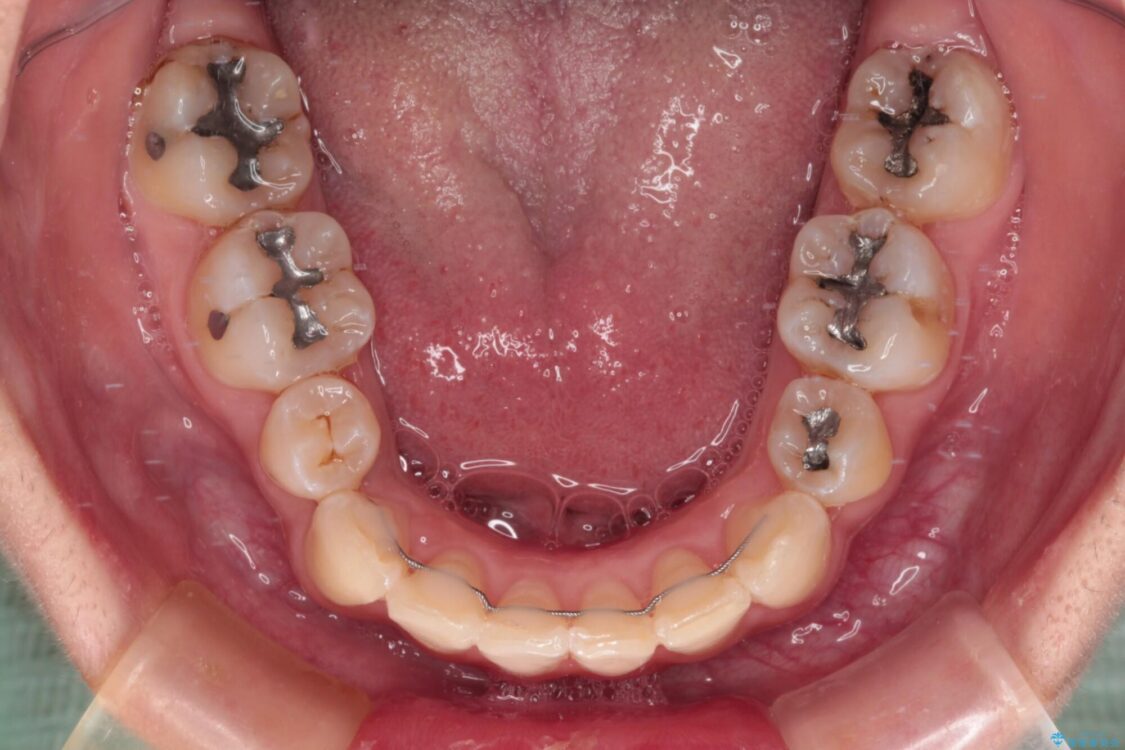

治療途中

• デコボコと深い咬み合わせ ワイヤー装置での抜歯矯正 治療途中画像

咬み合わせが深く、そのままでは上顎の抜歯スペースが閉じきらない可能性があったため、治療初期から深い咬み合わせを改善させるように試みました。

実際にはなかなか改善されず、当初予定よりも治療期間がやや長期化してしまいました。